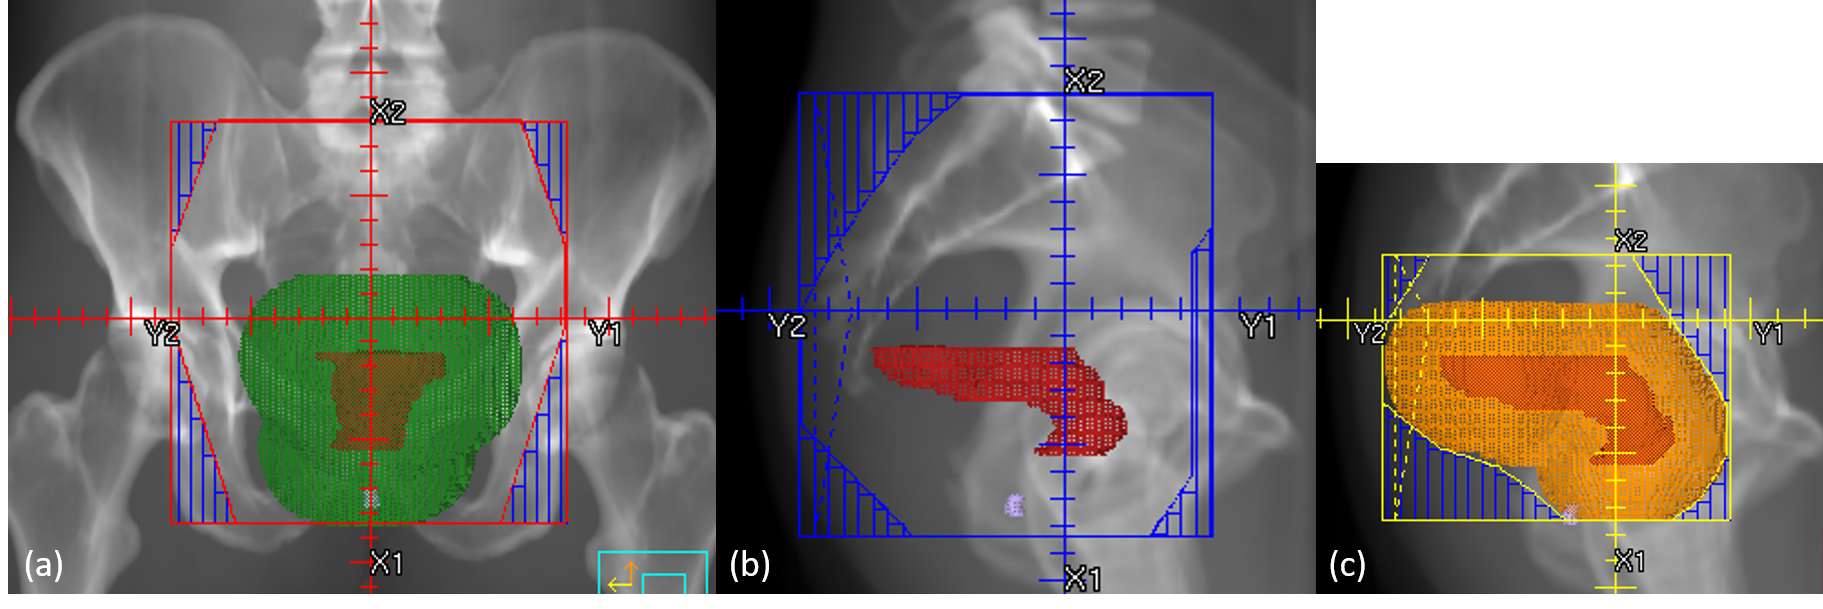

Our clinical practice uses bony anatomy and the locations of GTV and GTVn to determine the field apertures. The information about bony landmarks is derived from digitally reconstructed radiographs (DRRs) at each beam angle. Figure 1 illustrates how field apertures are determined for each beam angle in our clinic. Specifically, primary beams include a posterior–anterior (PA) beam and two opposed lateral beams. For the PA beam (Figure 1a), its superior border is set at either the L5/S1 intervertebral body intersection or 2-cm superior to GTV or GTVn,whichever is more superior.The inferior border is set at either the bottom of the obturator foramen or 3-cm inferior to the GTV, whichever is more inferior. The lateral borders are set at similar-to\sim2 cm from the pelvic brim. Once the borders are decided for the PA beam, the four corners of the field aperture are blocked off to prevent excessive dose to the sacroiliac joint and femoral heads. The primary lateral beams include left (LT) and right (RT) laterals and are usually mirror images of each other (Figure 1b). The superior and inferior borders of lateral beams match with those of the PA beam. The posterior border of the lateral beams covers the entire sacrum and extends 1-cm posterior to the sacrum. The anterior border of the lateral beams extends to 3-cm anterior to the sacral promontory, or 2-cm anterior to GTV or GTVn, whichever is more anterior. The boost beams (Figure 1c) are also opposed lateral beams, including both left (BstLT) and right (BstRT) laterals. The boost fields should include the GTV,GTVn,and adjacent pelvic and presacral regions to GTV and GTVn.

Refer to caption

Figure 1: The figure shows the clinical guidelines for field aperture placement, including primary beams and boost beams. The primary beams have one posterior–anterior (PA) beam and two opposed lateral beams. The boost beams have two opposed lateral beams. The opposed lateral beams are mirror images of each other: (a) PA beam, (b) primary right lateral beam, and (c) right boost beam. The red structure is gross tumor volume (GTV), the green structure is 3-cm uniform expansion of GTV, and the orange structure is 2-cm uniform expansion of GTV.